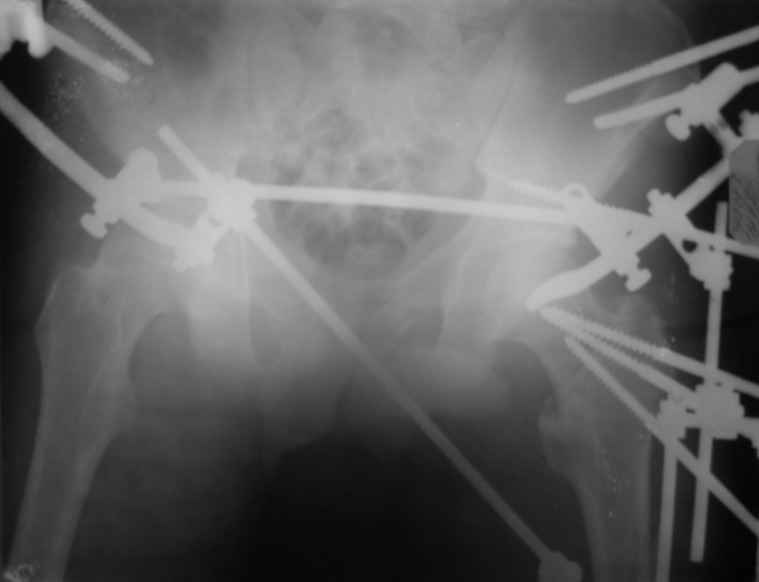

Вот снимки по свежей ситуации, парень 19 лет, длинный оскольчатый перелом бедра от шейки до в-с/3. давно уже ходит на своих ногах.

Представленные Вами рентгенограммы действительно являются примером качественной фиксации спице-стержневым аппаратом. Они, как ни что другое, многое иллюстрируют.

Кроме того, было бы ошибкой ставить знак равенства между нашим и Вашим пациентами. Они не только не похожи, разница между ними просто огромная. Говорю это не для того, чтобы задеть Вас или обидеть. Ни в коем случае. Просто теперь я понимаю, что Ваше мнением строится на простом преломлении Ваших подходов к лечению пациентов со свежими переломами, на ситуацию, абсолютно несопоставимую, подобную нашей.